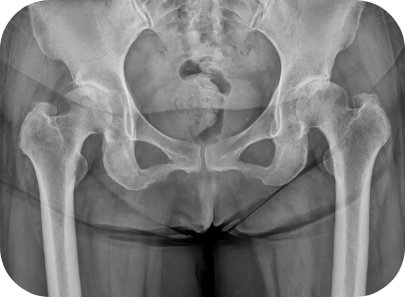

고관절 무혈성괴사 환자의 인공관절 전치환술 사례

• ▲ 수술 전

고관절 퇴행성관절염 환자의 인공관절 전치환술 사례